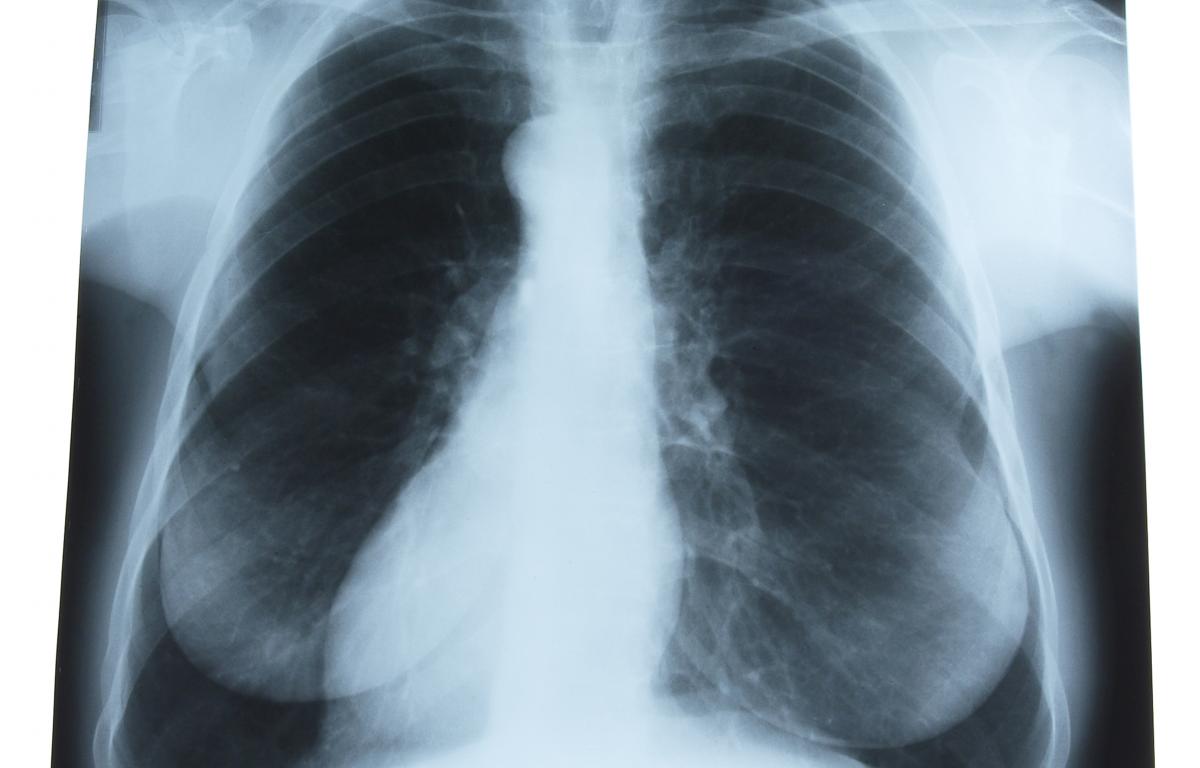

Lung cancer is in the news again as Rush Limbaugh announced he has lung cancer. But is it a death sentence? Dr. Morhaf Al Achkar of UW Family Medicine, who is living with stage 4 lung cancer himself, joins the Morning Show to discuss treatments and living with cancer.